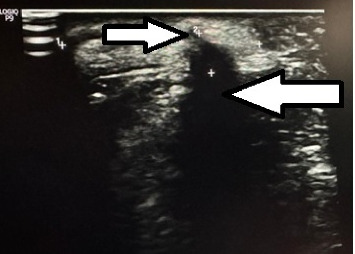

Background: Teratoma is a tumor usually consisting of tissues derived from multiple germ layers. A congenital teratoma occurring in the region of the head and neck is rare with barely 10 reports in the global literature since 1996. Of further rarity is its mandibular location. This probably represents the first report of its kind in the world in addition to being the first one to be reported from Nepal. Case Presentation: We report a case of an 11-month-old infant with a congenital appendage over the side of the chin that was treated with surgical excision and histologically confirmed as mature teratoma. Conclusion: Congenital facial teratoma in the mandibular location is a rare event. A principle combining appropriate surgical technique and correct oncological principles keeping esthetic appearance in mind is necessary for the best outcome.